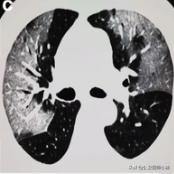

根据感染的不同程度累积一个或多个肺叶

肺部感染涉及多个肺叶-1

肺部感染涉及多个肺叶-2

肺部感染涉及多个肺叶-3

当涉及到一个或多个肺叶,肺功能的影响并不严重时,呼吸急促和呼吸困难的症状也并不严重。随着病情的发展,肺部实变开始吸收,密度降低逐渐变成毛玻璃样的混浊,像融化的糖。